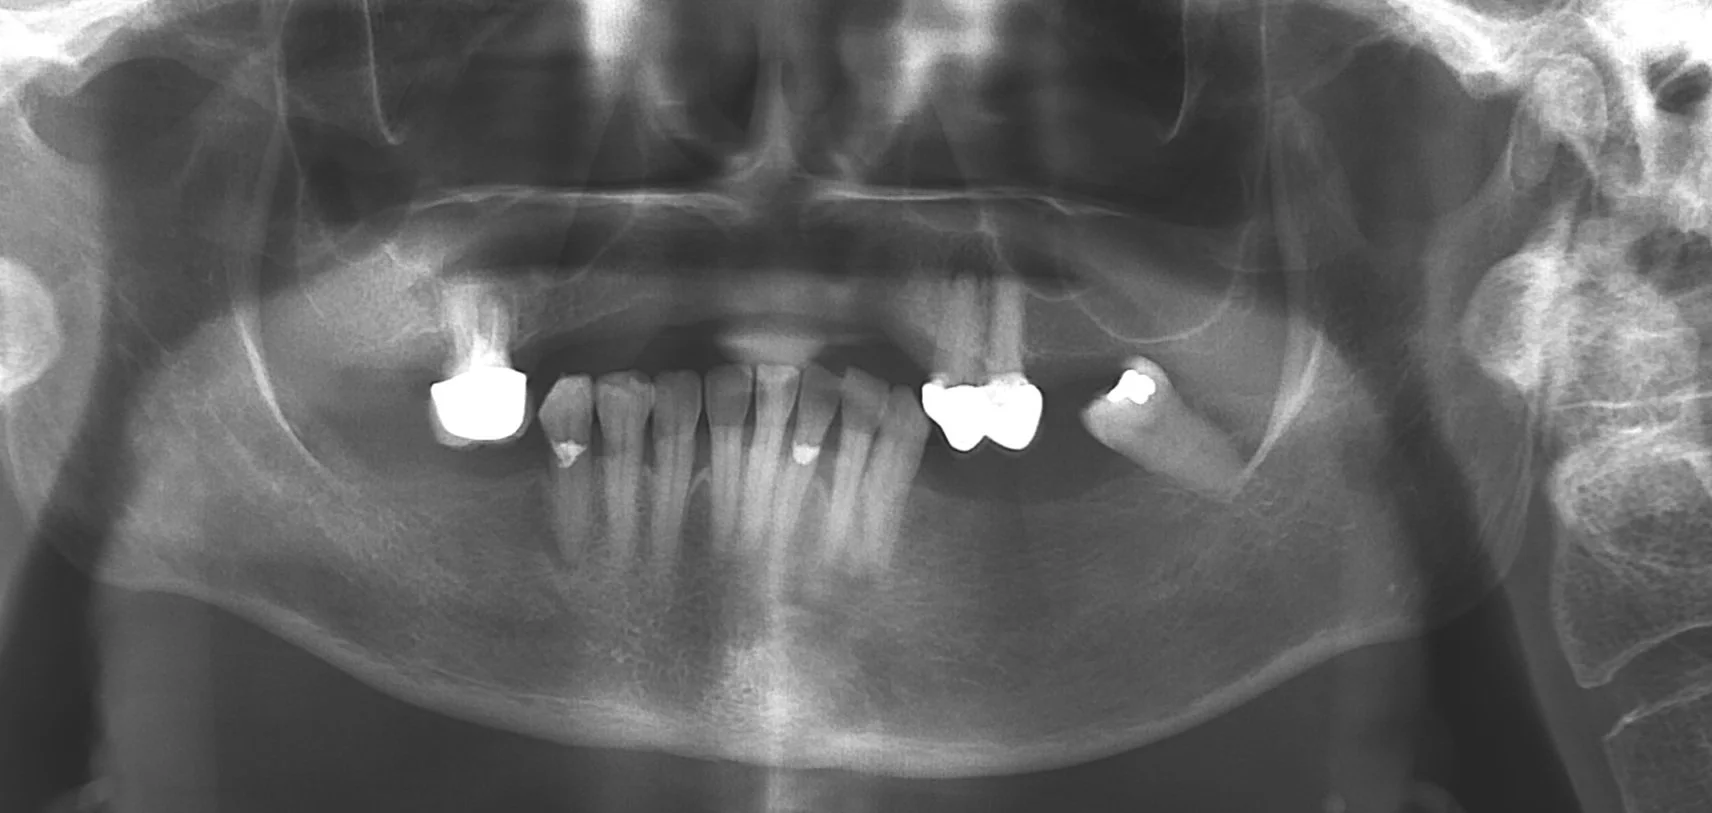

Panoramic dental X-ray showing upper and lower teeth with some dental restorations, including crowns and fillings, and the surrounding jawbone.